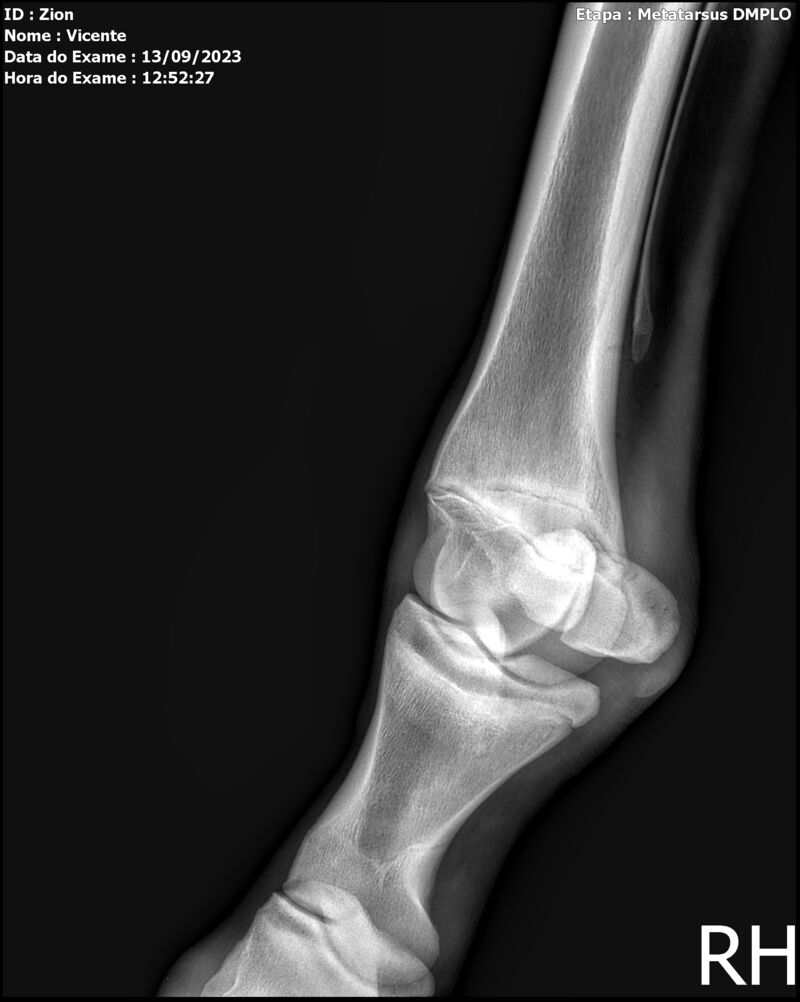

ZION ZC

Raça: BRASILEIRO DE HIPISMO

Sexo: MACHO - POTRO

Nascimento: 17/12/2022

Altura Aproximada: 1,51

Pel.: CASTANHO

Registro: EM AND

Vend.: VICENTE CONTE

Local : PORTO FELIZ/SP